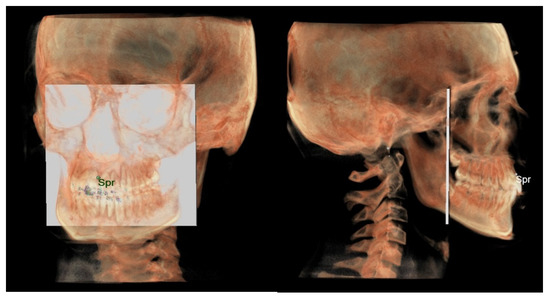

- Maxillary and Mandibular dento-alveolar arches (Figure 2): this parameter compares the lengths of maxillary and mandibular dento-alveolar arches. The maxillary dental arch was measured by the distance between PM and SPr, in parallel with Ref. The mandibular dental arch was measured by the distance between the orthogonal projection of IPr on Ref and Ara, at its intersection point with Ref.

- The maxillary dento-alveolar arch (Figure 8) was measured from the point SPr to a plane passing through the PNS and parallel to the coronal plane.